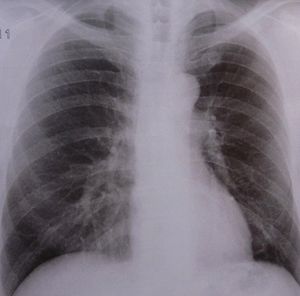

Lungen-Röntgen: Forscher finden neuen Diagnoseweg (Foto: pixelio.de, D. Schütz) |

Neapel (pte001/11.09.2014/06:00) Das zum Nationalen Forschungsrat CNR gehörende Istituto di Chimica Biomolecolare http://www.icb.cnr.it hat ein innovatives Verfahren zur Diagnose von zwei einander sehr ähnlichen Lungenpathologien entwickelt. Es handelt sich dabei um die Zystische Fibrose (Ziliendyskinesie) und die Mukoviszidose, die zu den am weitverbreitetsten chronischen Erkrankungen des Lungenapparates gehören. Die neue nichtinvasive Methode öffnet den Weg für eine gezielte medikamentöse Behandlung.